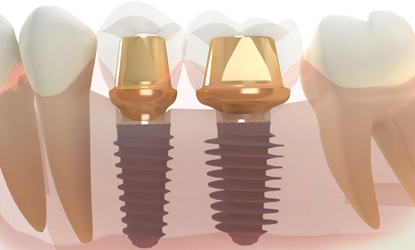

A dental implant is a small titanium screw that is placed in the jaw to act as a fixed and permanent root. During the healing process this screw integrates with the surrounding bone (through a process known as osseointegration) to create a strong and lasting foundation that can then be used to support a dental crown, multiple bridge, or fixed denture.

What is an implant?

Step 03

Abutment placement

The abutment is the connecting element between the crown and the implant.

The abutment is connected to the implant during or after the healing period, depending on the stability of the implant that gradually integrates with the surrounding bone to create a strong and lasting foundation.